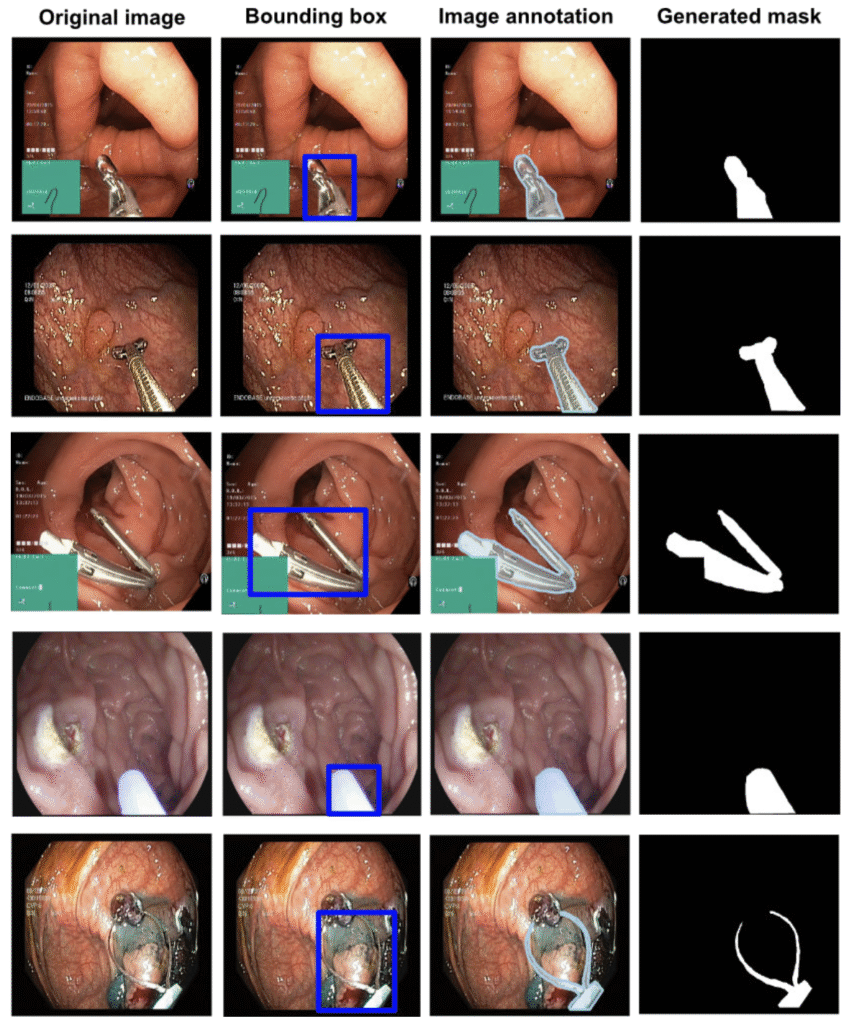

Kvasir-Instrument

590 endoscopic tool images with ground-truth masks and bounding boxes; foundational for automatic tool segmentation.